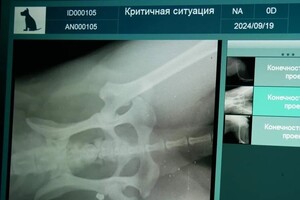

«Она скулила от боли, бежала через весь парк, истекая кровью, а потом еще долго тряслась от страха и шока. Глубокое проникновение в заднее бедро. Скорее всего, кусок холодного металла навсегда останется в теле этого умного доброго животного. Надеемся, что заражения и дальнейших осложнений удастся избежать. Лечение начато», – говорится в сообщении зоозащитницы.

Оплатить рентген и ветеринарные препараты для лечения раненого животного помогли неравнодушные. Заявление в полицию написали в тот же день. Комментариев по поводу этого инцидента правоохранители пока не предоставляли.